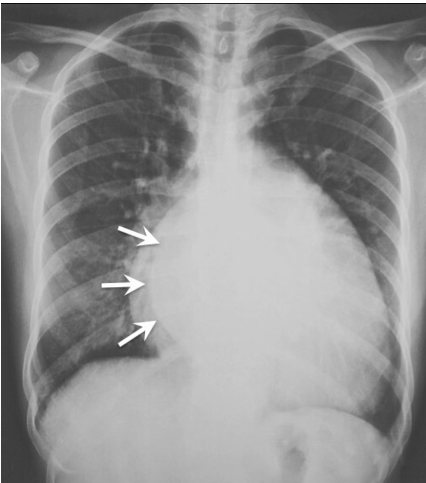

The x-ray given in the question shows the _____ sign suggestive of LA enlargement